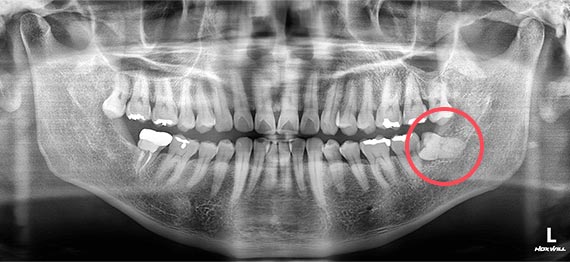

음식물이 어금니 뒤로 껴서 잇몸이 붓는 경우